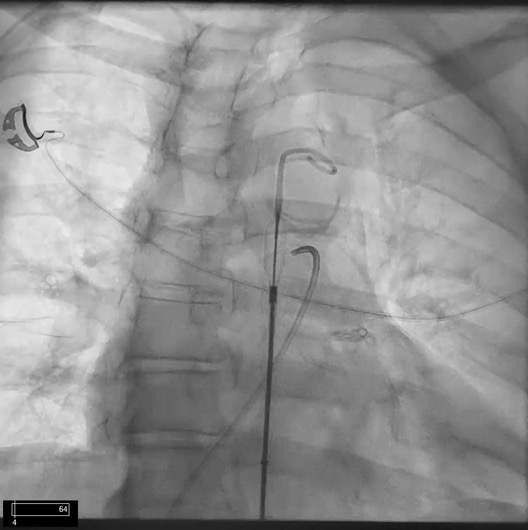

First Successful Use Of 2 Axial Flow Catheters For Percutaneous Biventricular Circulatory Support As A Bridge To A Durable Left Ventricular Assist Device Circulation Heart Failure